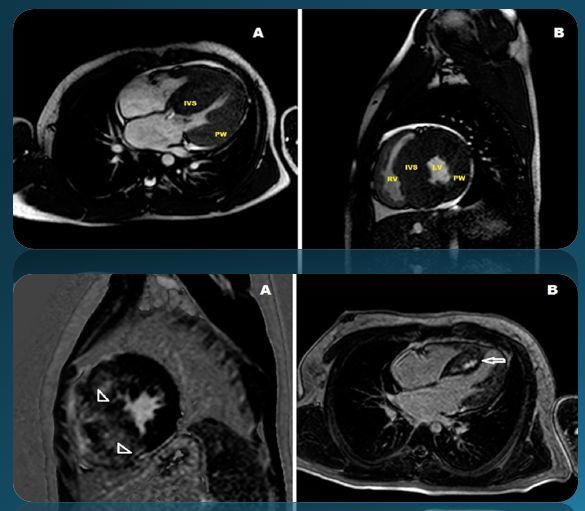

肥厚型心肌病

什么是肥厚型心肌病?